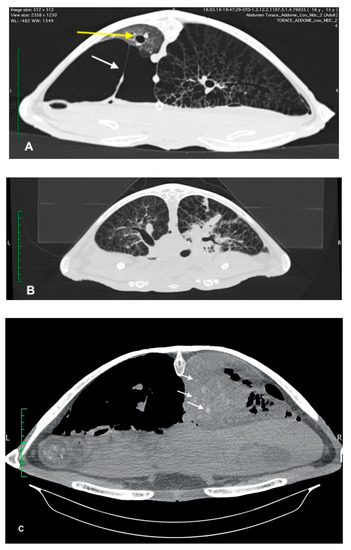

Four sea turtles underwent advanced diagnostic investigations with MDCT examination to better characterize the pulmonary pattern. This allowed the investigators to carry out a more precise identification of the areas of pulmonary consolidation. Moderate to severe pneumonia, pneumocoelom and pulmonary reticular pattern were found in all sea turtles.

In three sea turtles, the pneumogastric and pneumohepatic ligaments were stretched due to severe pneumocoelom that crushed the lung parenchyma against the carapace (Figure 2). In two turtles, the dorso-lateral displacement of the trachea and main bronchus was observed.

Figure 2. Transverse CT images of 3 loggerhead sea turtles: (A) severe left pneumocoelom stretched the pneumogastric ligament (white arrow) and compressed the left lung, with dorsal dislocation of the lung parenchyma and the main bronchus (yellow arrow). In the right lung a honeycomb pattern can be seen. (B) Patchy areas of consolidation of the ventral aspect of the lungs secondary to inflammatory process are evident, mostly in the right lung. (C) “CT angiogram” sign is present in the right lung—opacified vessels are visible within the consolidated lung following the infusion of intravenous contrast (arrows).